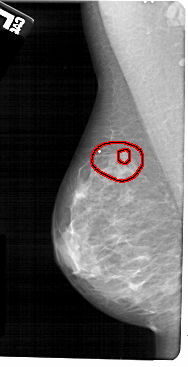

FILE: A_1673_1.LEFT_CC.OVERLAY

TOTAL_ABNORMALITIES 1

ABNORMALITY 1

LESION_TYPE MASS SHAPE IRREGULAR MARGINS SPICULATED

ASSESSMENT 5

SUBTLETY 4

PATHOLOGY MALIGNANT

TOTAL_OUTLINES 2

BOUNDARY

CORE